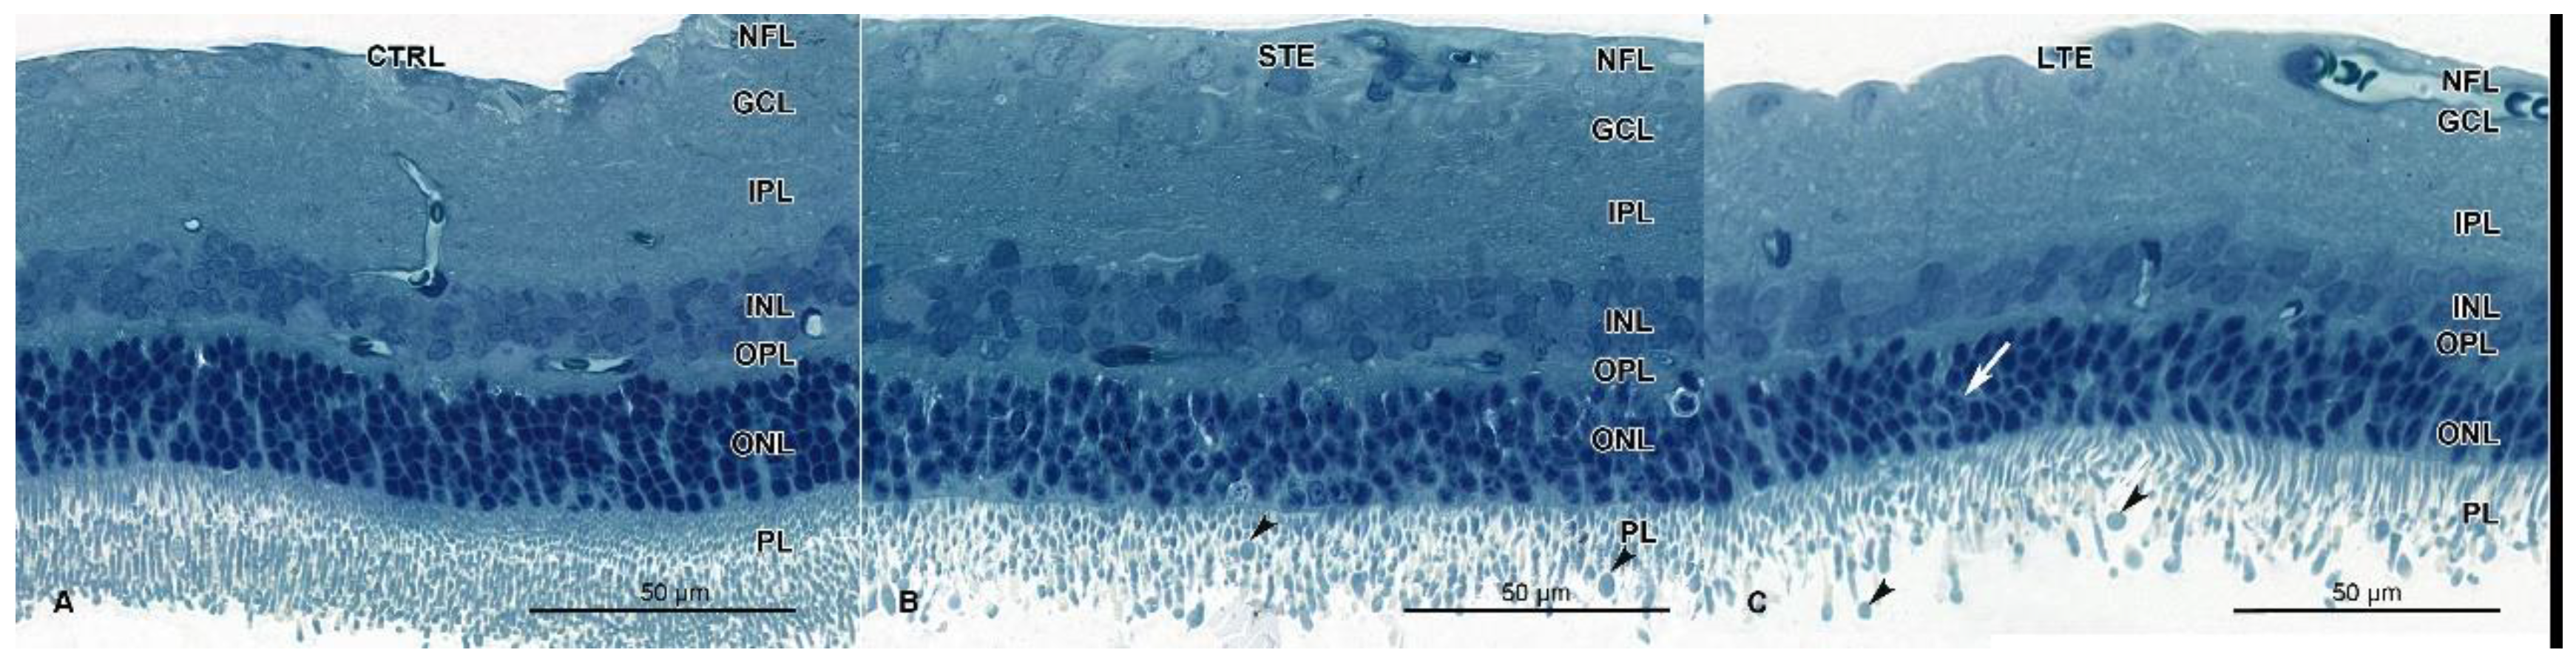

3.5. Retinal Damage after Exposure to Blue Light